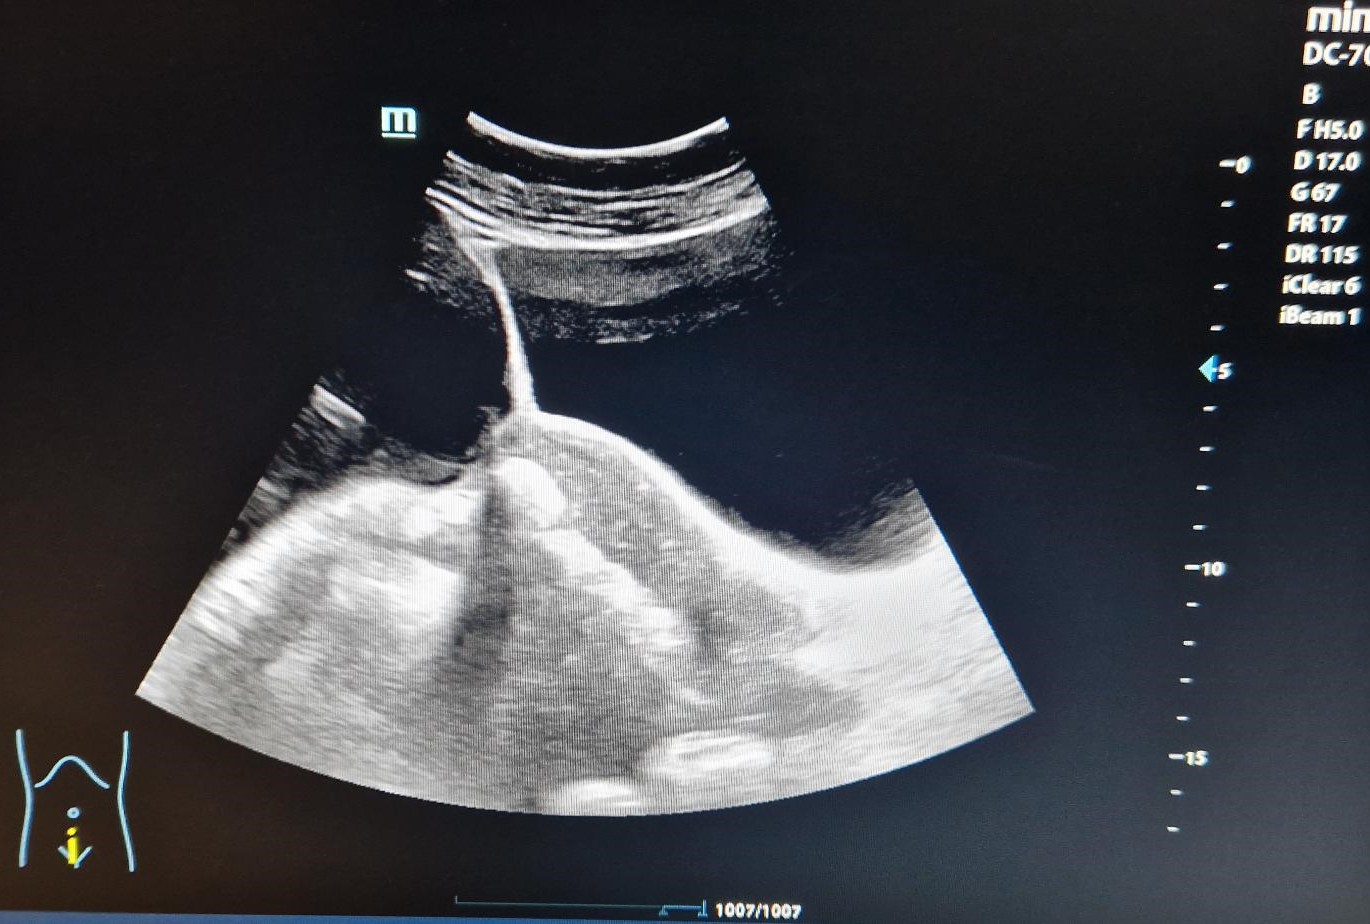

Eco abdomen: Masa anecoica con refuerzo posterior de gran tamaño con particulas en su interior, multilobulada y con tabiques en su interior que ocupa desde epigastrio, desplazando al páncreas, hasta mesogastrio, fosas ilíacas e hipogastrio, muy difícil determinar las medidas.

Informe Eco TV: útero en AV con endometrio de aspecto glandulo quístico de 9,6 mm (impresiona de pólipo endometrial). Douglas y ambas regiones anexiales ocupadas por formación quística de gran tamaño (280 x 93 x 190 de lateralidad no determinable) no abarcable en su totalidad ni con sonda abdominal. Dicha formación es multilobular, con tabiques de grosor variable (el mayor de 6 mm) vascularizados sin papilas, de cápsula regular y fina en porción más próxima a ambas fosas ilíacas. No líquido libre.